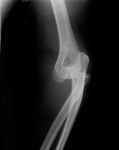

Visão lateral de radiografia de luxação posterolateral do cotovelo

Acervo pessoal do Dr. Paul Novakovich